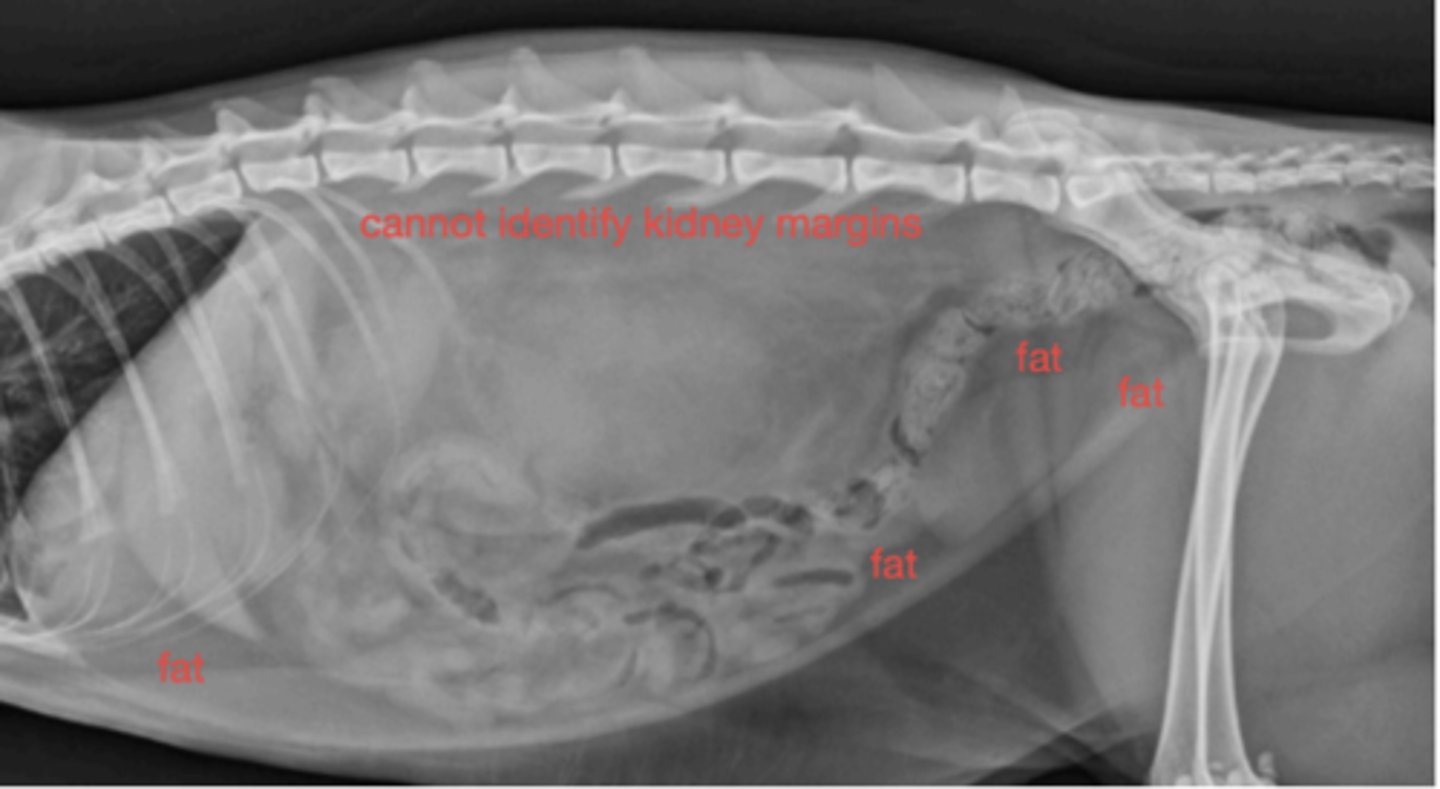

Radiograph; can't see much in abdomen - why?

Fat

What are these opacities on the cat?